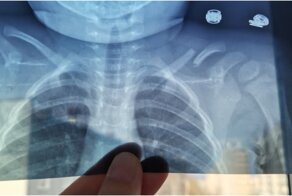

Документ важный. Он должен устанавливать правила для национальных запасов лекарств. В случае необходимости у больниц будет небольшой лекарственный запас, но у страны в целом нет. Кто пострадает от жадности властей? Как всегда, люди.